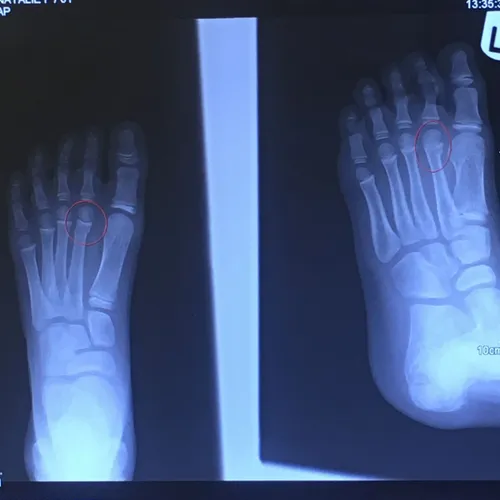

Pediatric Displaced 5th Met Distal shaft/neck fracture

Preop Pics of the displaced fracture prior to Percutaneous Fixation and Reduction

We percutaneously put a pin across the fracture after closed reduction for 12-16 weeks. The last picture is a final after the fracture is healed and the pin is removed.